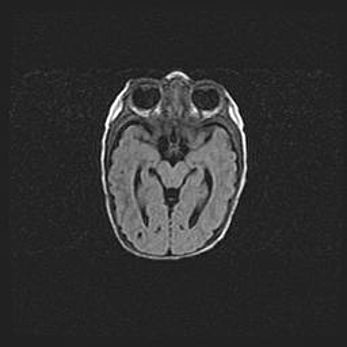

Церебральная ишемия II.

Возраст: 7 дней

Вес: 3350 г

Пол: женский

Окружность головы: 35 см

Срок гестации: 39 недель

Ишемия головного мозга – это состояние, которое развивается в ответ на кислородное голодание вследствие недостаточного мозгового кровообращения. У новорожденных она является следствием дефицита кислорода, что ведет к метаболическим расстройствам различной степени тяжести в тканях головного мозга, в том числе к развитию коагуляционных некрозов и гибели нейронов.